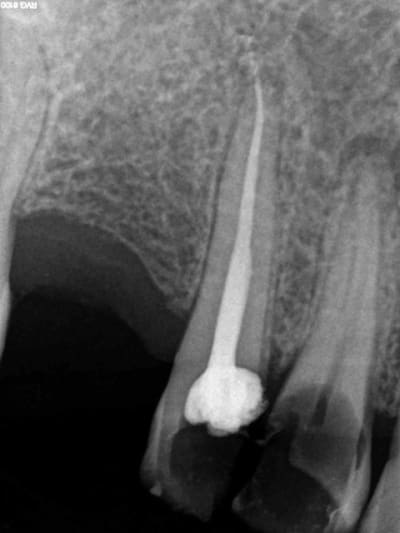

Aujourd'hui patient en urgence ca tombe bien pour une fois synchro avec un lapin.

45 mn de turbinage intensif 2 endos + 2 SC 33; On cote comment les radios ?

Z6, SC 20, Z3,Z3, SC20, Z3, Z3, SC 33, Z3, SC 33, Z3 ?